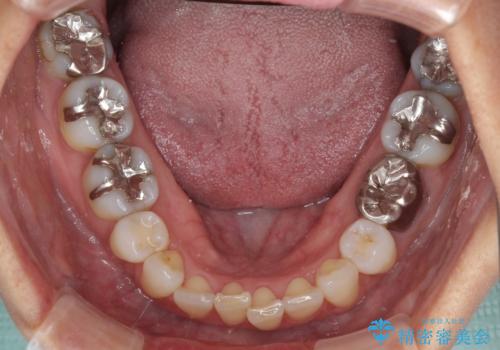

- 口を開けたときに目立ってしまう銀歯をセラミックに替えたいとのことで来院された患者様です。

上顎や親知らずにも銀歯がありましたが、今回の治療では目立つ下顎の銀歯4歯をセラミッククラウンやセラミックインレーに置き換えることにしました。